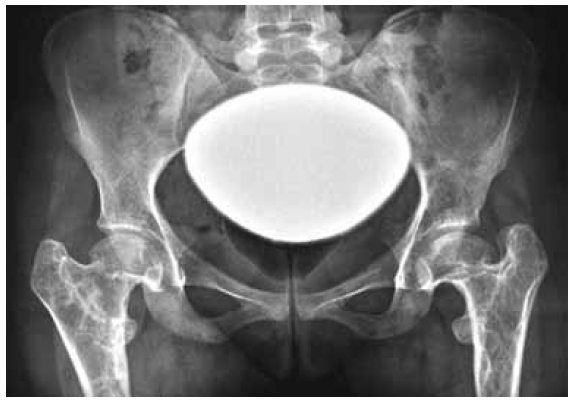

Radiographic examination: AP radiograph of the pelvis showed bilateral coxa vara associated with expansile lytic lesion with ground glass matrix was seen bilaterally involving the proximal femora shaft and the greater trochanter with significant deformity seen in the proximal femoral region. Ring-like calcification suggesting cartilage was well appreciated. Note the hypoplastic capital femoral epiphyses and the defective modelling of the neck of the femur. There is a shortage of the femoral neck with pathologic ATD (articular trochanteric distance) of (minus) 7 mm left and (minus) 5 mm right (Fig. 1).

Fig. 1. AP radiograph of the pelvis showed bilateral coxa vara associated with expansile lytic lesion with ground glass matrix was seen bilaterally involving the proximal femora shaft and the greater trochanter with significant deformity seen in the proximal femoral region. Ring-like calcification suggesting cartilage was well appreciated. Note the hypoplastic capital femoral epiphyses and the defective modelling of the neck of the femur. There is a shortage of the femoral neck with pathologic ATD (articular trochanteric distance) of (minus) 7 mm left and (minus) 5 mm right